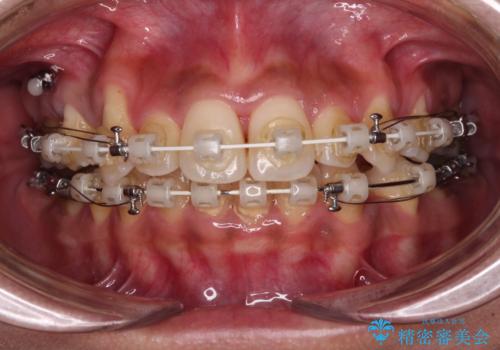

- 審美装置

- 八重歯と上下前歯のでこぼこを気にして来院された患者様です。

上下前歯部叢生のスペース獲得のため、上下顎左右小臼歯各1歯(計4本)を抜歯して、ワイヤー装置にて矯正治療を行うこととしました。

上下の正中位置が大きくずれていたため、上下正中が合わないまま終了することが予想されましたが、思っていた以上にスムーズに歯が移動し、満足いただける仕上がりとなりました。